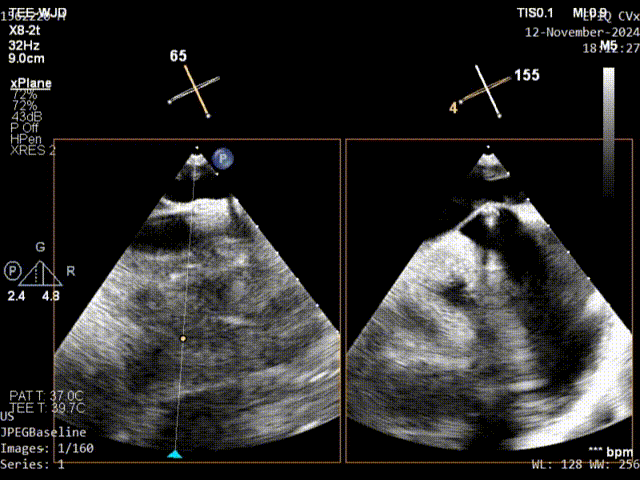

原发隔第二针缝合

术中通过调整缝线松紧度观察有无右向左分流,确认无分流以后一键完成打结、切线、脱离操作,通过超声确认锁结的位置无移位、形态稳定,无残余分流。

锁前确认